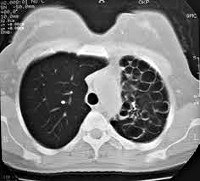

Рентгенограммы выявляют деформацию или усиление рисунка кистозной доли или сегмента, имеющих характерную ячеистую структуру за счет многочисленных тонкостенных, различных по диаметру бронхиальных расширений, чередующихся с участками паренхимы или почти целиком заполняющие объем недоразвитой ткани. Крупные бронхи обычно не изменены. Объем гипоплазированной доли легкого снижен, граница средостения подтянута в ее сторону. КТ легких дает более четкое представление об объеме и распространенности кистозных деформаций и воспалительных изменений.